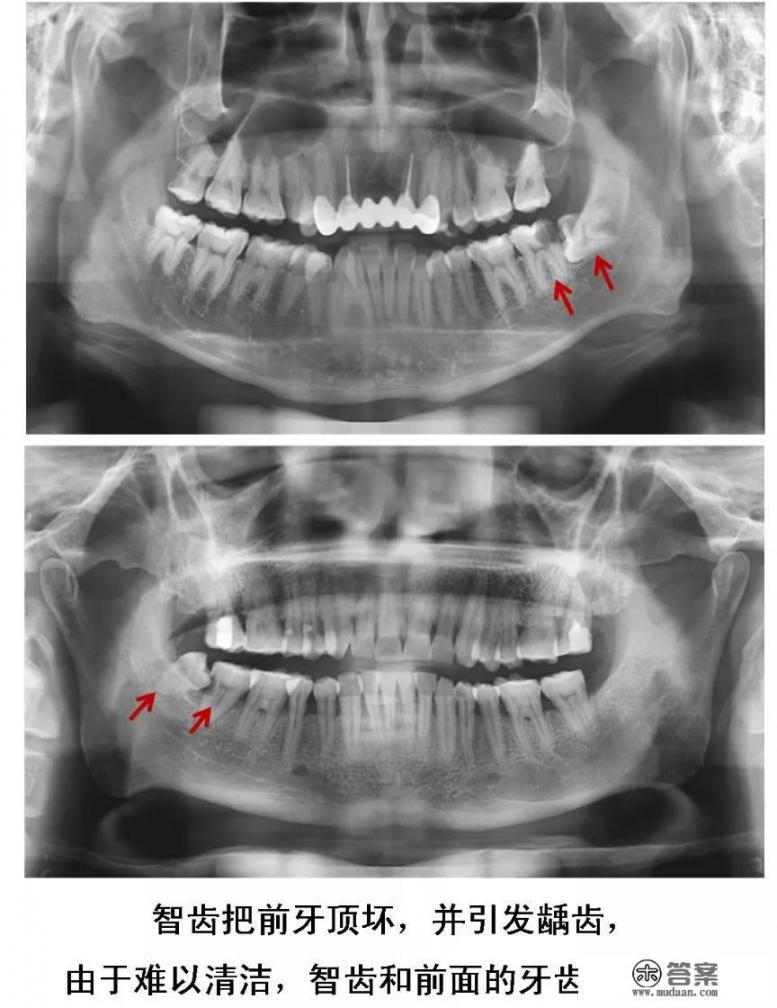

2、长歪的阻生智齿

当智齿没有足够空间生长,脱离“轨道”,与邻牙之间产生缝隙,容易嵌塞食物,滋生细菌,引起蛀牙。

或是智齿生长的方向正好顶住邻牙,时间久了不仅会把邻牙顶坏,龋坏进一步发展会造成牙髓炎。